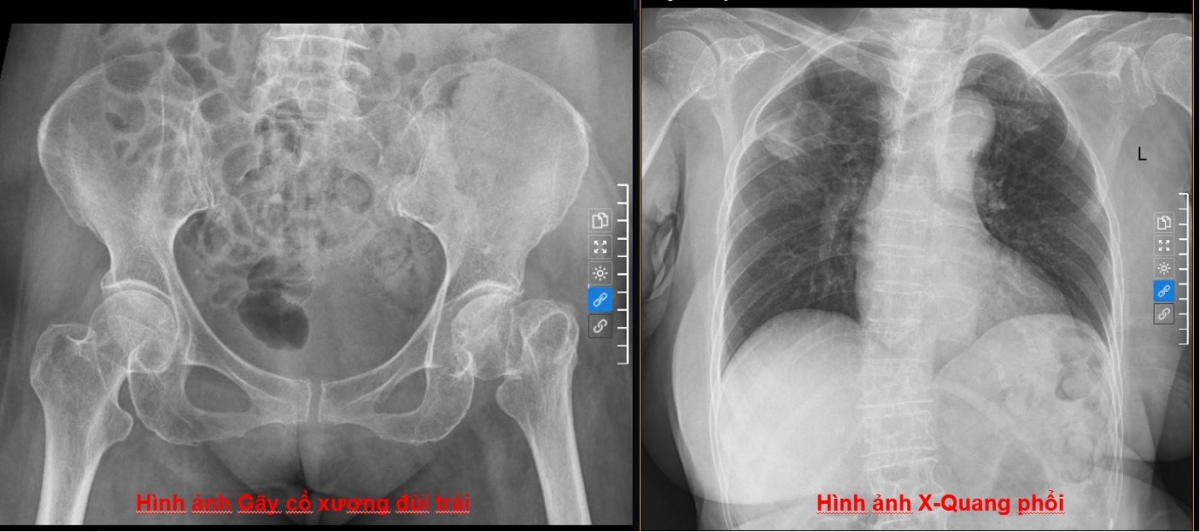

Tỷ lệ tử vong tới 30% sau gãy cổ xương đùi ở người cao tuổi

VOV.VN - Chỉ một cú ngã nhẹ trong sinh hoạt thường ngày, người cao tuổi có thể đối mặt với gãy cổ xương đùi – chấn thương nguy hiểm với tỷ lệ biến chứng và tử vong cao. Phát hiện sớm, điều trị đúng và can thiệp kịp thời là yếu tố quyết định tiên lượng.

Ở người cao tuổi, chỉ một cú trượt chân trong sinh hoạt thường ngày cũng có thể dẫn đến gãy cổ xương đùi – một trong những chấn thương nghiêm trọng và phổ biến nhất trong nhóm bệnh lý cơ xương khớp.

Theo thống kê y khoa, tỷ lệ gãy cổ xương đùi gia tăng rõ rệt theo tuổi, đặc biệt ở nhóm trên 70 tuổi, do loãng xương và suy giảm thăng bằng.

Đáng lưu ý, khoảng 20–30% người bệnh cao tuổi có thể tử vong trong vòng 2–3 tháng sau chấn thương. Nguyên nhân chủ yếu liên quan đến các biến chứng do nằm bất động kéo dài như viêm phổi, tắc mạch và loét vùng tỳ đè.